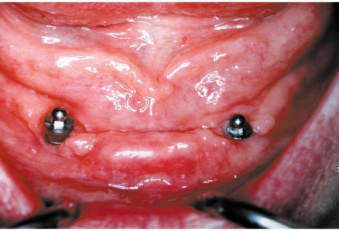

Bezzubá čelist je hlavní indikací pro ošetření pomocí implantátů. Zejména celkové zubní náhrady v dolní čelisti mají velice nízkou stabilitu a držení díky velkému úbytku kosti.

S pomocí zubních implantátů můžeme díky různým kotevním systémům (třmeny, kulové hlavy, Locatory) zajistit stabilitu a držení protézy nebo při použití většího počtu implantátů zhotovit pevné náhrady – můstky nalepené nebo našroubované na pevno na implantáty.